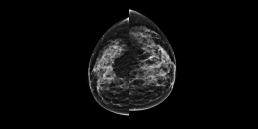

Femme de 52 ans , mammographie de dépistage.

MammoscreenTM pointe une lésion rétromamelonnaire du sein droit.

La biopsie confirme un carcinome canalaire infiltrant SBR 2, R+